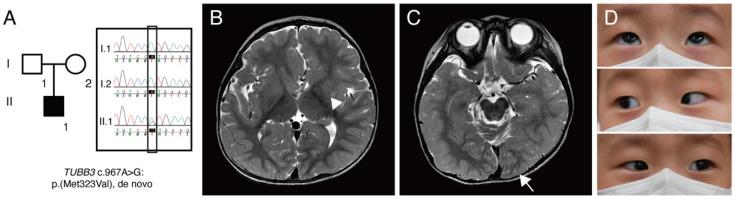

Variants in the gene, one of the tubulin-encoding genes, are known to cause congenital fibrosis of the extraocular muscles type 3 and/or malformations of cortical development. Herein, we report a case of a 6-month-old infant with c.967A>G:p.(M323V) variant in the gene, who had only infantile nystagmus without other ophthalmological abnormalities. Subsequent brain magnetic resonance imaging (MRI) revealed cortical dysplasia. Neurological examinations did not reveal gross or fine motor delay, which are inconsistent with the clinical characteristics of patients with the M323V syndrome reported so far. A protein modeling showed that the M323V mutation in the gene interferes with αβ heterodimer formation with the gene. This report emphasizes the importance of considering and tubulinopathy in infantile nystagmus. A brain MRI should also be considered for these patients, although in the absence of other neurologic signs or symptoms.

该基因中的变体,即微管蛋白编码基因之一,已知会导致 3 型先天性眼外肌纤维化和/或皮质发育畸形。在此,我们报告了一例 6 月龄婴儿携带 基因中的 c.967A>G:p.(M323V)变体,该婴儿仅表现为婴儿性眼球震颤,无其他眼科异常。随后的脑磁共振成像(MRI)显示皮质发育不良。神经学检查未发现粗大或精细运动延迟,这与迄今为止报道的 M323V 综合征患者的临床特征不一致。蛋白建模表明, 基因中的 M323V 突变会干扰与 基因形成的αβ异二聚体。本报告强调了在婴儿性眼球震颤中考虑 和 微管蛋白病的重要性。对于这些患者,即使没有其他神经体征或症状,也应考虑进行脑部 MRI。